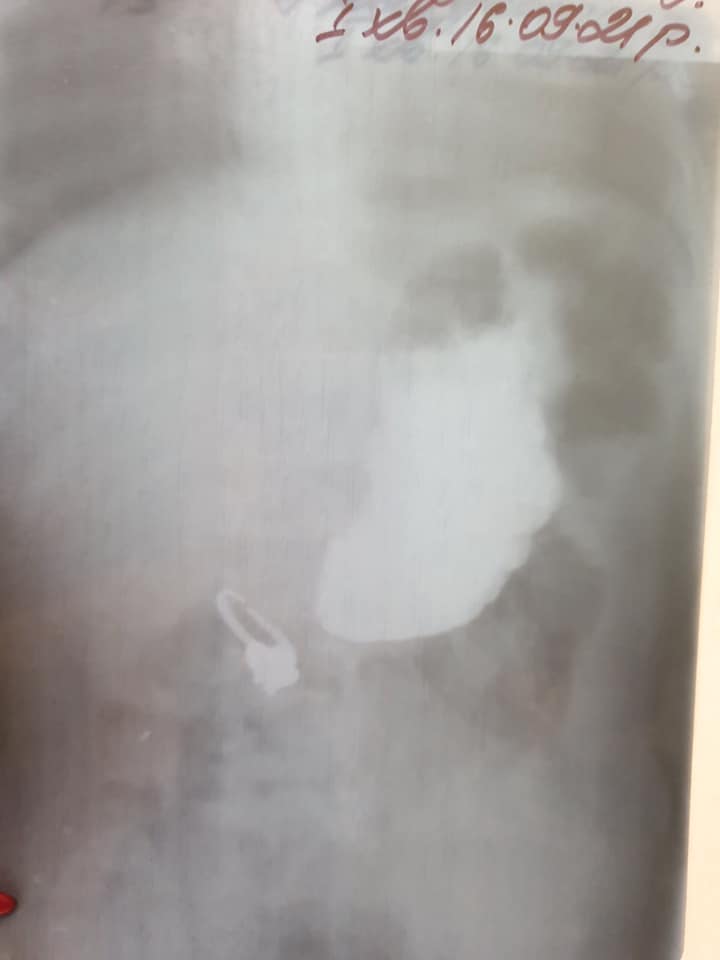

Як повідомили у дитячій лікарні «Охматдит», дівчинка гралася зі сестрою і в якийсь момент менша спробувала перстеник на зуб, старша хотіла забрати його з рота сестрички і випадково проштовхнула його глибше. На рентгені хірурги побачили, що перстень розірваний посередині і має гострі кінці.

Перстень потрапив у дванадцятипалу кишку і частину кишки гострим краєм затягнув всередину, що ускладнювало ситуацію.

«Перстень постійно зачіпався гострими краями за краї кишки, але нам вдалося дістати його без операції. Правда, маніпуляція була досить тривалою, ми з ним змагались близько 2 години», – зазначила лікарка-ендоскопіст Марта Лучак.